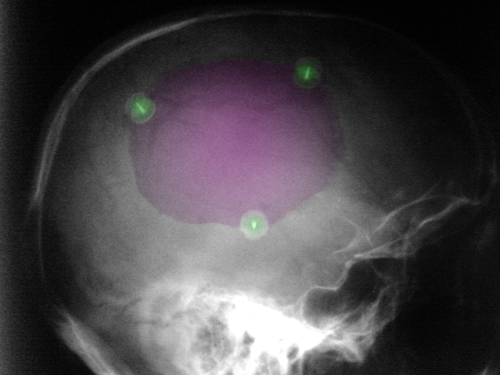

Κρανιοπλαστική (μώβ). 3 στηρικτικά κλιπ τιτανίου με πράσινο. |

Περιγραφή Η επέμβαση γίνεται υπό γενική αναισθησία. Κατά κανόνα χρησιμοποιείται η υπάρχουσα δερματική τομή της κρανιεκτομίας. Ο δερματικός κρημνός αποκολλάται από την υποκείμενη μήνιγγα έως τις παρυφές του οστικού ελλείμματος. Η αποκατάσταση γίνεται με την τοποθέτηση ή του οστού που είχε αφαιρεθεί στην κρανιεκτομία ή με συνθετικό εμφύτευμα. Στην πρώτη περίπτωση πρέπει να έχει προηγηθεί φύλαξη του οστού σε βαθειά ψύξη και κατόπιν απολύμανση με ακτινοβολία. Σπανιότερα μετά την κρανιεκτομία γίνεται φύλαξη του αφαιρεθέντος οστικού τεμαχίου με μετεμφύτευση στο υποδόριο του κοιλιακού τοιχώματος. Εάν το οστικό τεμάχιο δεν έχει φυλαχθεί για πρακτικούς λόγους ή δεν μπορούσε να επαναχρησιμοποιηθεί λόγω καταστροφής του (από την προηγηθείσα κάκωση) τότε χρησιμοποιείται συνθετικό εμφύτευμα. Το συνθετικό εμφύτευμα μπορεί να πλασθεί από πολυμερές ακρυλικό (PMMA) διεγχειρητικά ή να τοποθετηθεί προκατασκευασμένο εμφύτευμα από πολυμερές το οποίο μπορεί να μορφοποιηθεί σε μέγεθος, σχήμα και καμπυλότητα. Υπάρχει επίσης και η δυνατότητα τοποθέτησης προκατασκευασμένου - με τη βοήθεια τρισδιάστατης ανασύνθεσης της αξονικής τομογραφίας του ασθενούς - συνθετικού μοσχεύματος το οποίο τοποθετείται ήδη μορφοποιημένο. Ο κρημνός (οστικός ή συνθετικός) στερεώνεται με στηρικτικές πλάκες ή clip από τιτάνιο ή τεχνητό οστό ή ράμματα. |